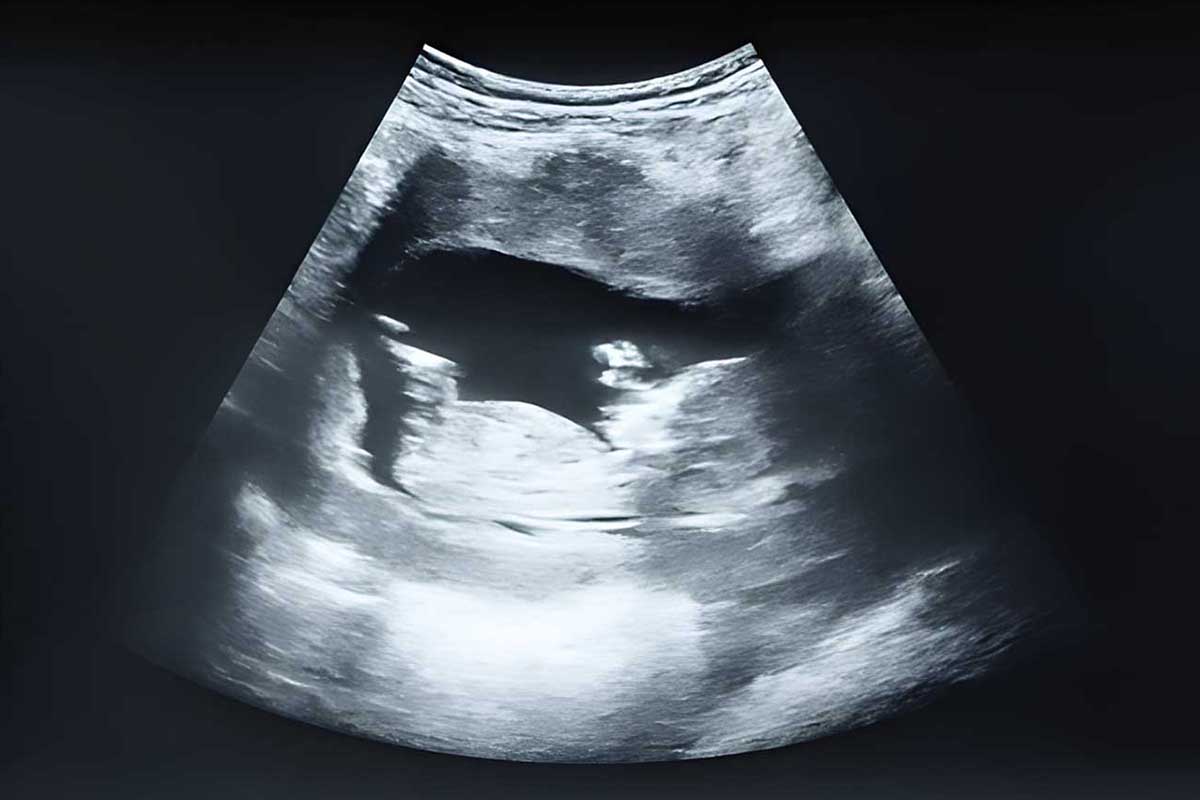

سونوگرافی در سه ماهه دوم بارداری

سونوگرافی باید در حدود هفته 20 انجام شود. این روش ساده است و تصویر جنین با استفاده از امواج صوتی به دست می آید. این سونوگرافی معمولا برای بررسی ساختار بدن جنین انجام می شود. مانند قلب، کلیه ها، اندام ها و سایر قسمت ها و می تواند حدود نیمی از ناهنجاری ها یا نقایص مادرزادی را تشخیص دهد.

در سونوگرافی سه ماهه دوم بارداری جنسیت جنین نیز مشخص می شود. قبل از انجام سونوگرافی می توانید تصمیم بگیرید که تا لحظه تولد از جنسیت نوزاد اطلاعی نداشته باشید، در این صورت حتما به سونوگرافی اطلاع دهید.